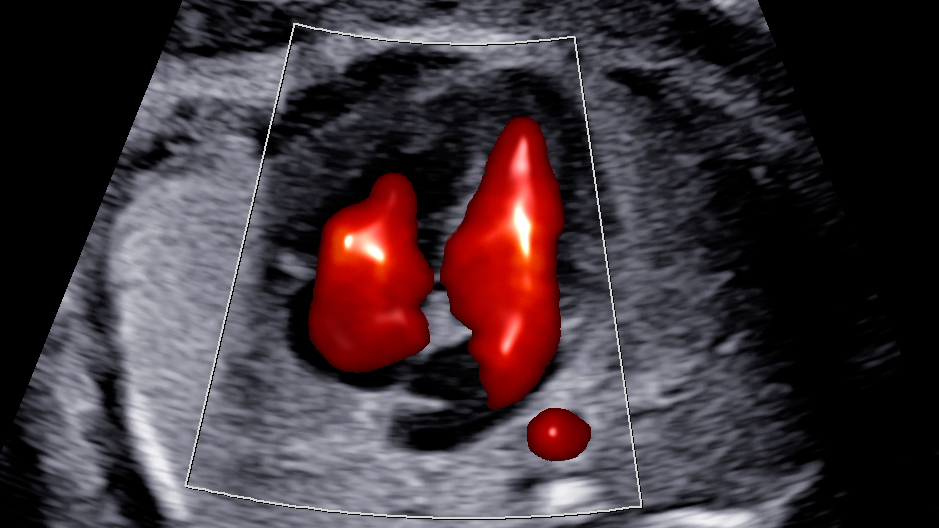

4) Coração

- Câmaras e válvulas

- Vasos principais e conexões

- Fluxos (quando necessário)